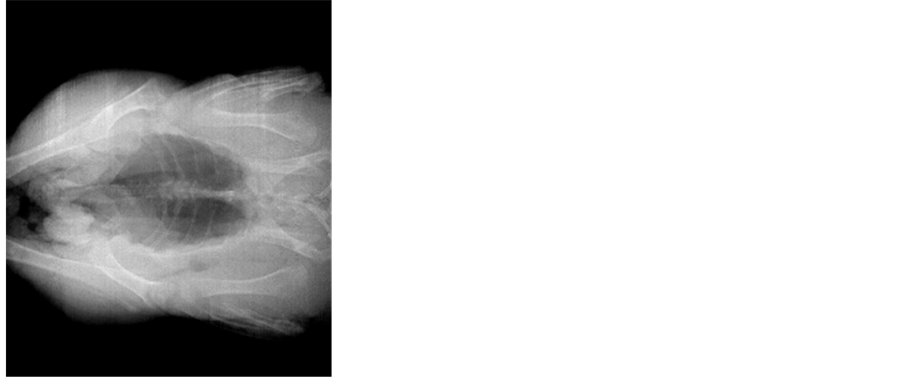

Images described below were obtained with 3 modules which have minimum pixel intensity fluctuation due to scanner array movement and defects in input channels of ASIC which affects on output signals. Raw image example with compensated dark currents is showed in Figure 6 together with adjusted sensitivity by using the ramp object calibration and by MIRE [14] algorithm. The scan was done from top to the bottom and the exposure time was 1.4 seconds. Algorithms which use only image data itself without additional information will leave artifacts in regions with significant intensity gradients.

Figure 6. Example of sensitivity adjustment, from left to right: raw image, adjusted with MIRE algorithm, adjusted using ramp object.

Examples of images before and after sensitivity adjustment are shown on Figure 8 from full length of linear array of 16 sensitive modules and 2048 sensitive elements. Resulted MTF is represented in Figure 9 for two rescale filters (Cubic and Lanczos) of raw image obtained with the same exposition parameters.

Figure 8. Examples of images before and after sensitivity adjustment.